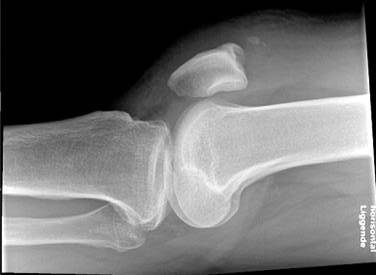

Rtg viser lavtstående patella: